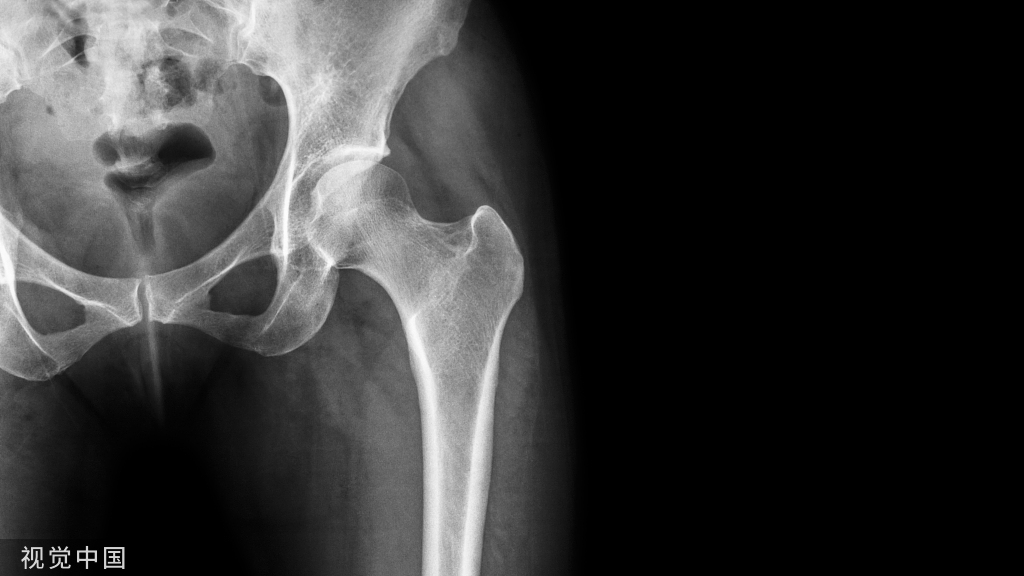

影像学表现

踝关节正位:距骨内侧结节至跟内载距突间有一长舍状骨块影,将跟骨与距骨连在一起,其间有一裂隙,形如关节,可以一侧明显。

踝关节侧位:跟骨距骨增大的两骨块呈唇状相吻,由后上斜向前下,内示裂隙。

特征影像:

C型征:是指跟距骨桥在侧位X线片,可见距骨头与载距突边缘轮廓组成环状高密度影。

展示一个跟距骨桥的病例